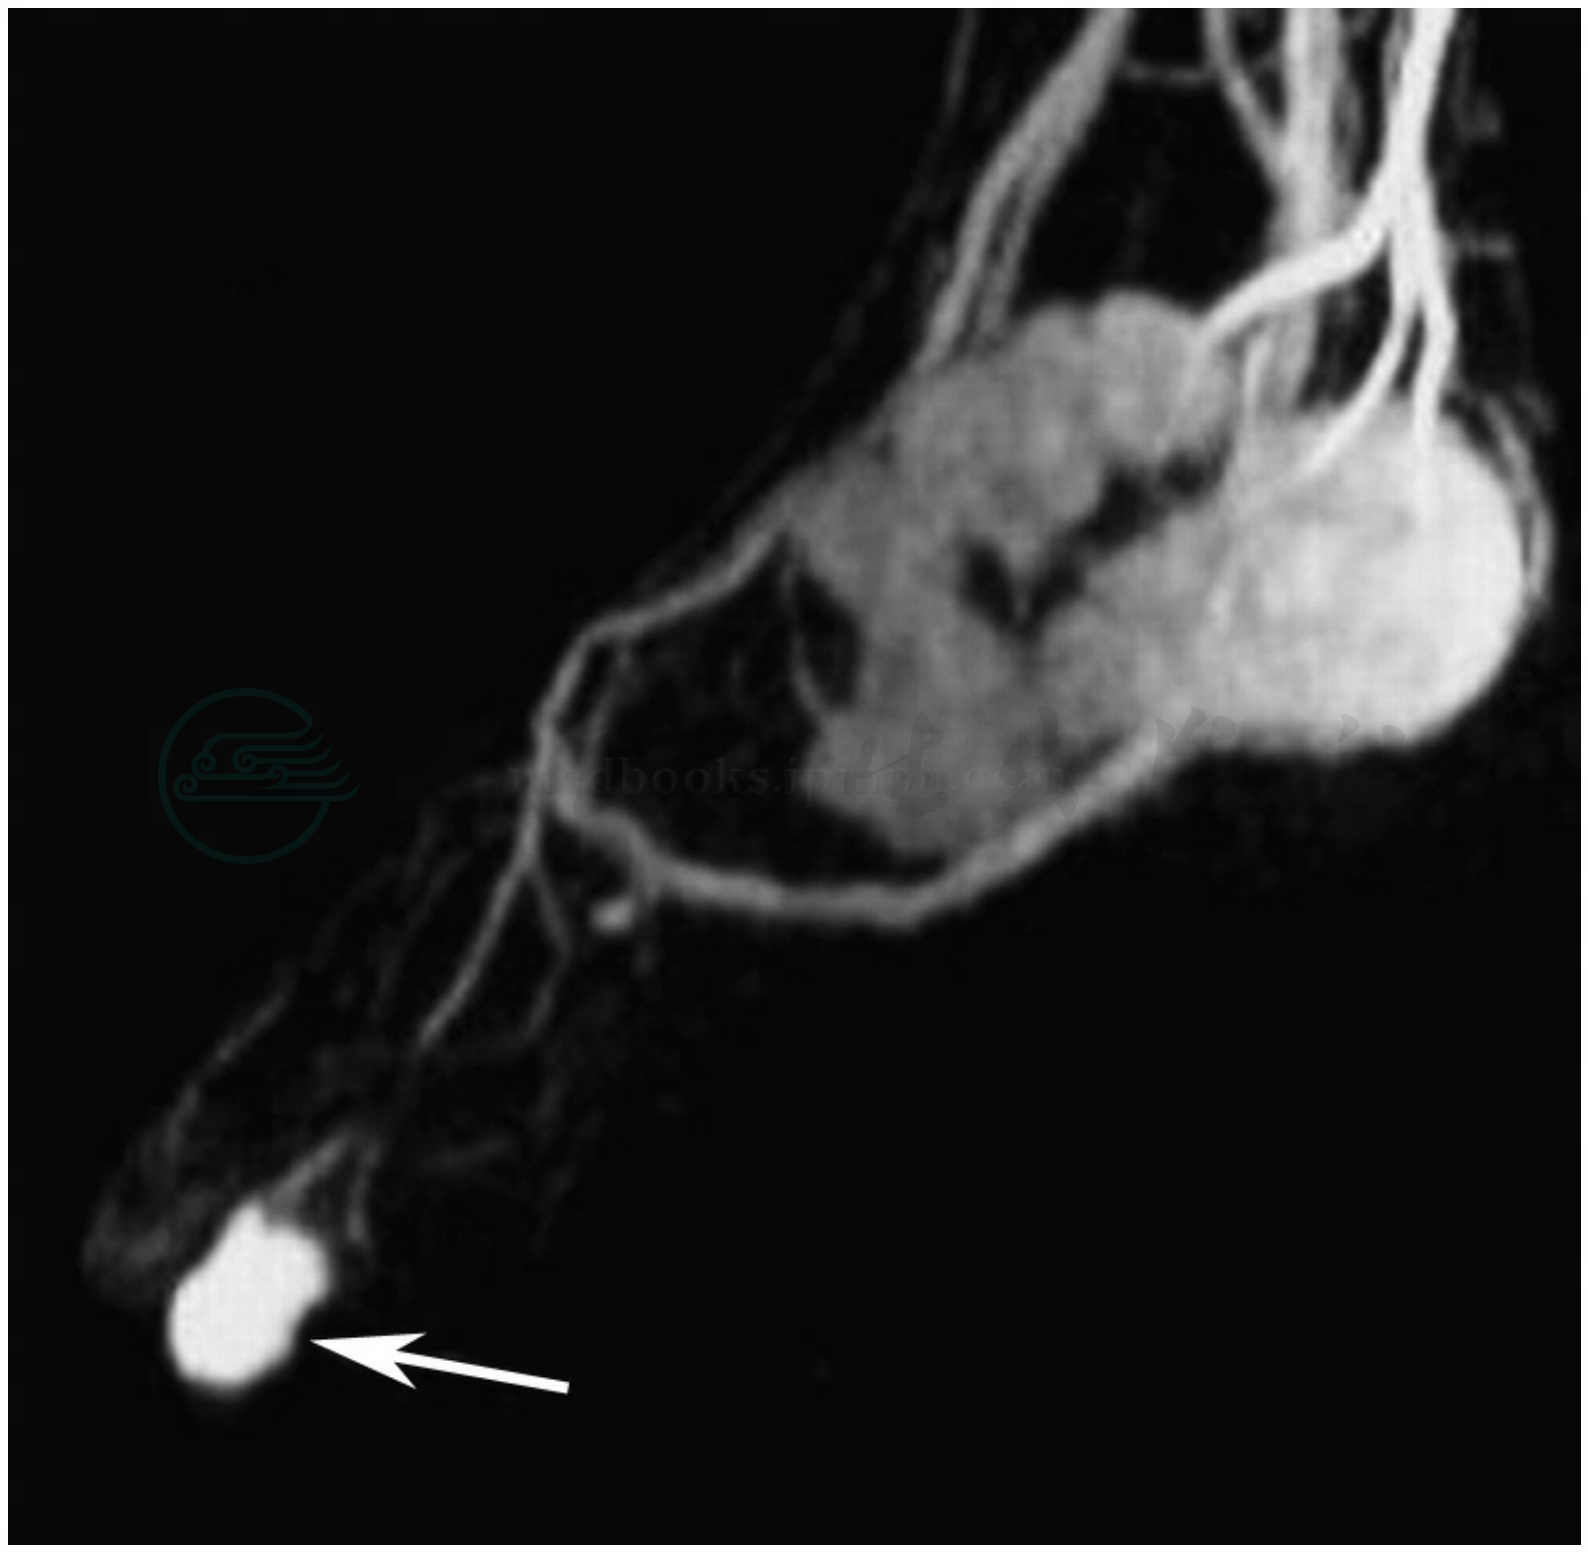

图6 血管瘤三期3D DCEMRA

注:动脉早期,瘤体轻微显影(箭头),供血动脉清晰(长箭头),静脉早显(短箭头)。